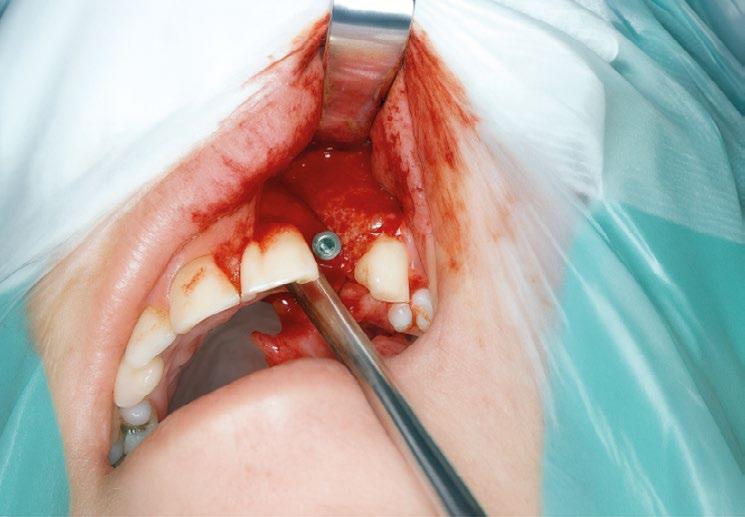

1.- Quitamos la corona ferulizada. (Figura 15)

2.- Extraemos de manera meticulosa la raíz del diente afectado. (Figura 16)

3.- Legramos toda la zona del lecho implantario con el fin de poder eliminar cualquier resto de tejido de granulación.

4.- Desepitelizamos en margen gingival. (Figura 17)

5.- Tunelizamos el defecto vestibular para alojar el injerto de tejido conectivo. (Figura 18)

6.- Colocamos injerto de tejido conectivo. (Figura 19)

7.- Interponemos membrana reabsorbible entre tejido conectivo y alveolo. (Figuras 20 y 21)

8.- Realizamos osteotomía mediante férula quirúrgica utilizando fresa piloto. (Figuras 22 a 24)

9.- Seguimos preparando el lecho utilizando fresado biológico con la OsseoShaperTM. (Figura 25)

10.- Colocamos implante Nobel Biocare N1TM TiUltra de 3,5x13. (Figura 26)

11.- Observamos el torque obtenido de 50N por lo tanto podemos realizar carga inmediata. (Figura 27)

12.- Colocamos aditamento N1TM Base XealTM con el fin de trabajar la prótesis a nivel gingivall. (Figura 28)